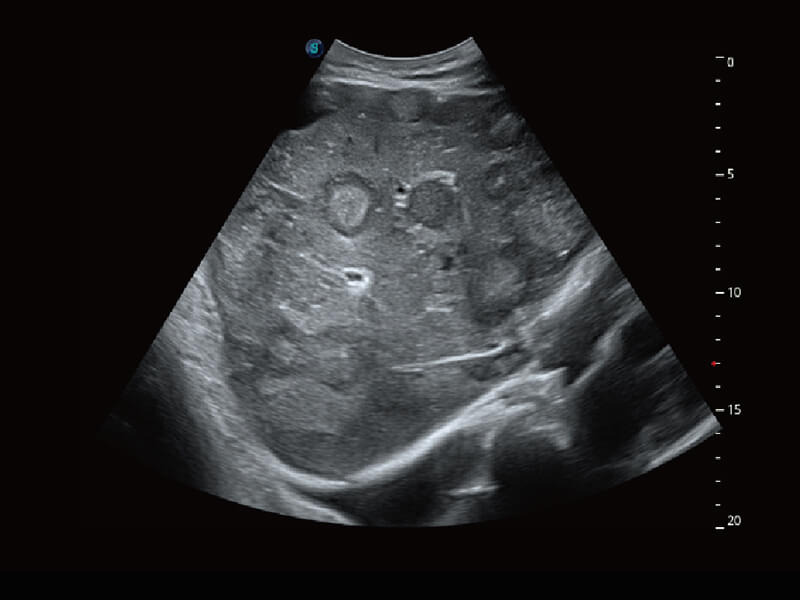

S60探头工艺,从前端信号处理每一个环节采集无损声学数据,真实还原组织原貌,再现解剖细节。

超宽频带技术,为容积成像带来优质的二维图像基础,为您呈现丰富的结构细节,栩栩如生地展示宝宝的宫内形态以及各种组织的立体结构。